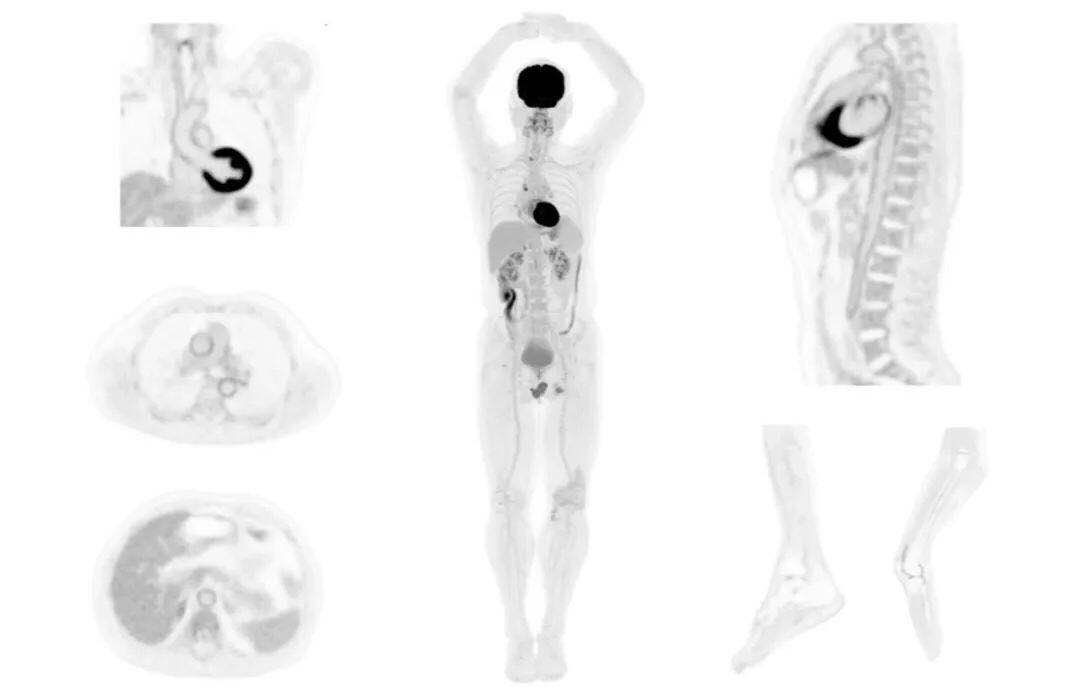

肺癌轉(zhuǎn)移及復(fù)發(fā)

患者男性,66歲,七年前發(fā)現(xiàn)右肺肺癌,其間手術(shù)兩次,共切除兩個肺葉,復(fù)查;

診斷意見,回腸轉(zhuǎn)移,右肺殘留部復(fù)發(fā)